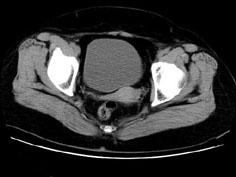

问题 女性,27岁,体检时B超发现右侧附件区囊性占位性病变,行CT检查,下列说法错误的是 ( )

选项 A、此为卵巢浆液性囊腺瘤 B、此为卵巢囊肿 C、病灶边界清晰 D、病灶为单房,壁薄,无分隔 E、病灶来源于右侧卵巢

答案 A